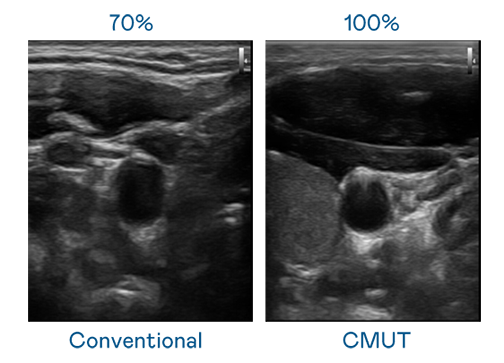

CMUT 技术是一种用电容式微机电元件来产生超音波讯号的技术。与传统 PZT 压电式技术相比,CMUT 频宽增加 30%,更宽频的超音波讯号让影像解析度大幅提升,是实现高影像品质医疗超音波扫描、促进精准医疗发展的关键技术。

超音波影像的解析度高低,首先取决于探头能发出的讯号频宽。不凡成就非凡 CMUT 可提供高清晰的超音波讯号,提供高频宽、高灵敏度、影像纹理细节更高的超音波影像,协助医护人员缩短影像判读时间及利用精准的医疗影像进行诊断。